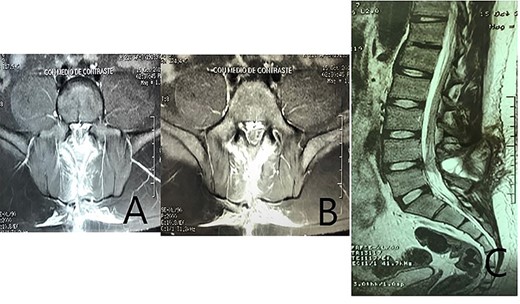

In the third month of follow-up visit, surgical wound was completely healed without signs of infection nor cerebrospinal fluid leakage; neurological examination remained normal; a standard postoperative magnetic resonance was obtained (Fig. 6).

A standard postoperative magnetic resonance imaging. (A–B) coronal T2 images show a posterior cumulus of fluid that seems to connect the epidural space with the subcutaneous tissue, at the L4–L5 space, related to the laminectomized level. (C) Sagital T2 image demonstrating a posterior cumulus of fluid at the L4–L5 space; no changes in the L4–L5 disc compared with adjacent levels, and scar tissue is visible within the dural sac. The image is highly suspicious of cerebrospinal fluid leakage; the origin of the leakage whether from the anterior or posterior surface of the dural sac is not clear.